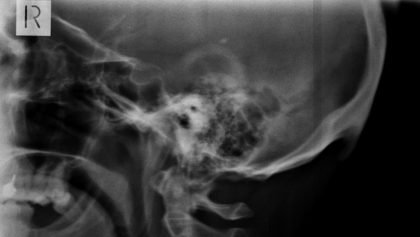

Se trata de un hueso en forma de pico, llamado protuberancia occipital externa, que aparece en la parte posterior de la cabeza, un poco por encima el cuello. Este puede sentirse al tacto y a veces incluso puede resultar visible en personas calvas.

Tras su descubrimiento, el científico decidió llevar a cabo unas investigaciones para determinar el alcance de la propagación de la anomalía. En 2016, lideró un estudio que analizó a 218 personas de entre 18 y 30 años de edad. El trabajo, publicado en la revista Journal of Anatomy, mostró que el 41 % de los participantes tenían en su cabeza ‘picos’ de más de 10 milímetros, mientras que en un 10 % de los examinados superaban los 20 milímetros.

En otra investigación, publicada en febrero de 2018 en la revista Nature, Shahar se centró en determinar la edad de las personas que contaban con ese tipo de formaciones. En el estudio participaron 1.200 individuos de entre 18 y 86 años, y el análisis concluyó que era «significativamente más probable» encontrar estas protuberancias entre los participantes de entre 18 y 30 años.

Cuando nos inclinamos sobre las pantallas, los músculos del cuello se tensan para sostener la cabeza, cuyo peso aproximado es de 4,5 kilogramos. En el lugar donde aparece este ‘pico’ se concentra una gran presión muscular, y los especialistas creen que el cuerpo trata de adaptarse para aliviar esta presión creando nuevos huesos que ayuden a repartir el peso de la cabeza por una superficie mayor.